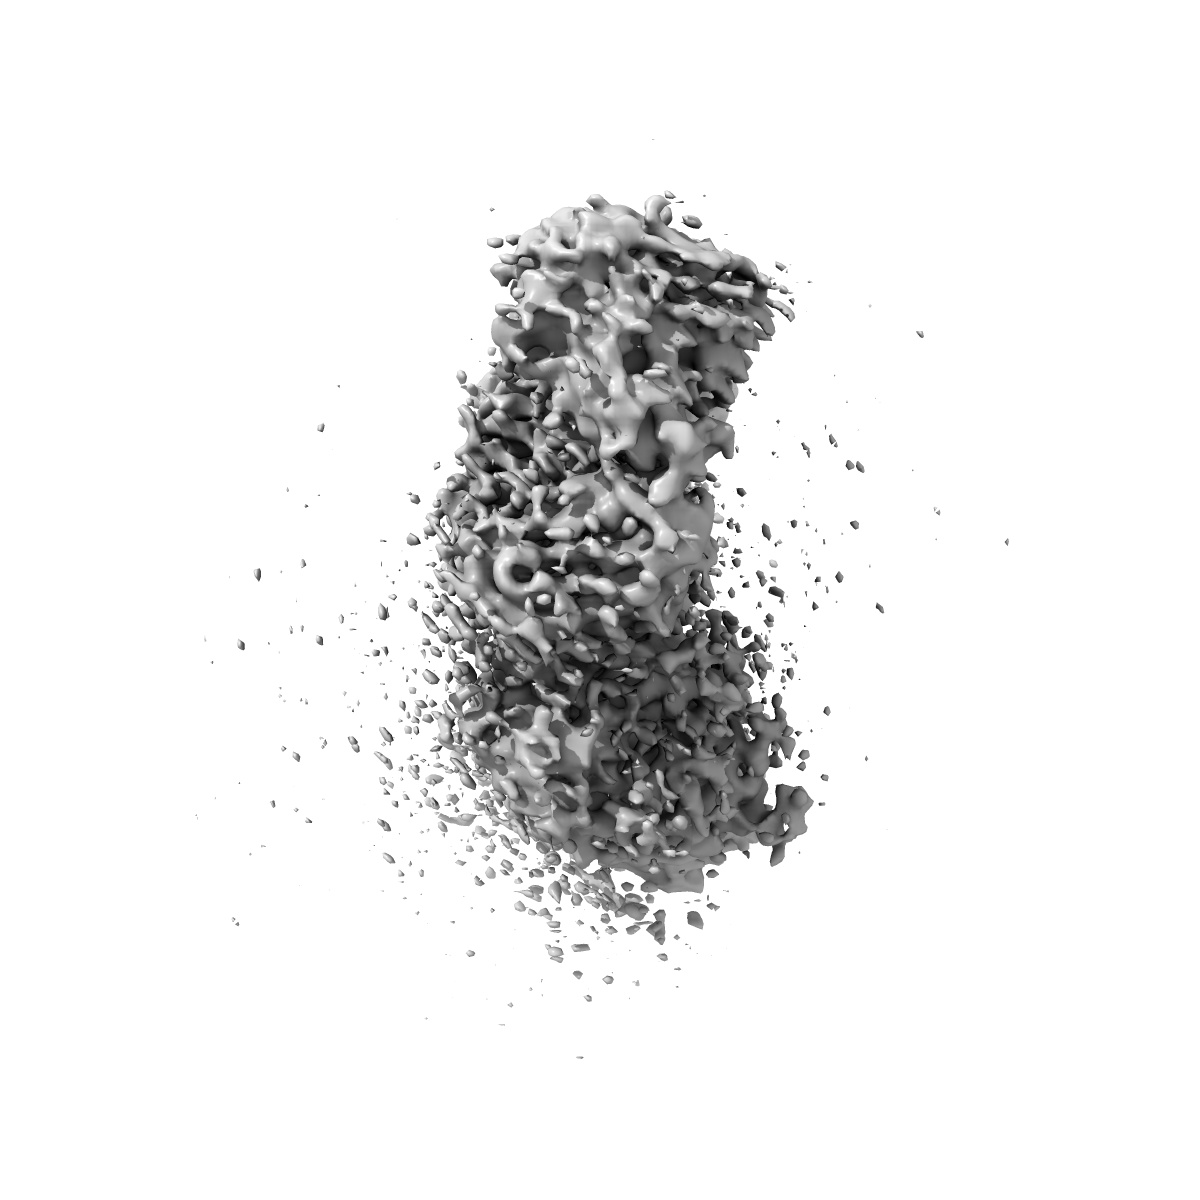

Cryo-EM structure of engineered hepatitis C virus E1E2 ectodomain in complex with antibodies AR4A, HEPC74, and IGH520

Sample Organism: Homo sapiens, synthetic construct, Hepacivirus C

Sample: HCV E1E2 ectodomain in complex with AR4A, HEPC74, and IGH520

Structure of engineered hepatitis C virus E1E2 ectodomain in complex with neutralizing antibodies.

Metcalf MC, Janus BM , Yin R , Wang R, Guest JD, Pozharski E , Law M , Mariuzza RA , Toth EA , Pierce BG , Fuerst TR , Ofek G

(2023) Nat Commun , 14 , 3980 - 3980